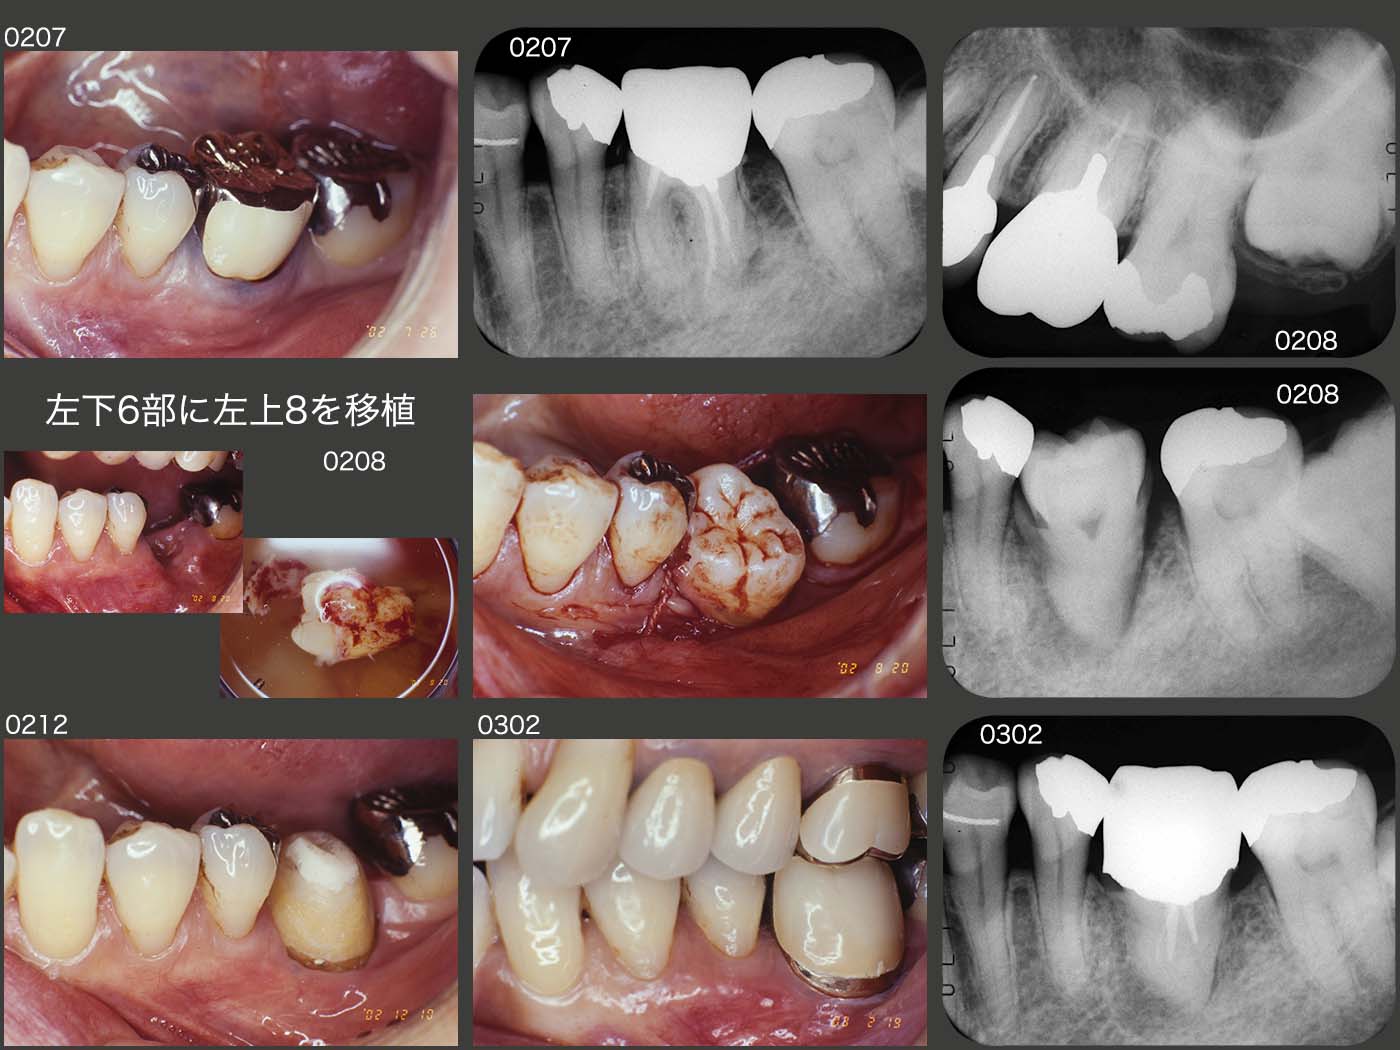

2002年7月,恐れていた左下6に急化Perが生じた.投薬および感染根管治療を行ったが,根尖を穿通することが出来なかった.今なら,再植をすると思うが(急性症状が落ち着いていたら矯正的挻出を先に行う.),当時は埋伏している左上8を左下6部に移植する方法を選択し,8月に実施した.03年2月,硬質レジン前装冠を装着した.